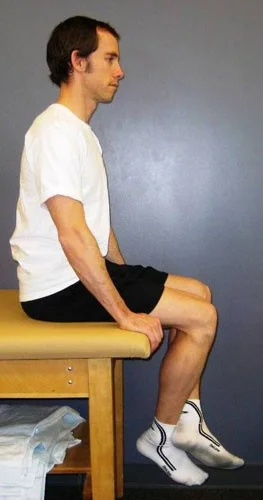

- Sitting comfortably on edge of couch, with knees flexed 90°